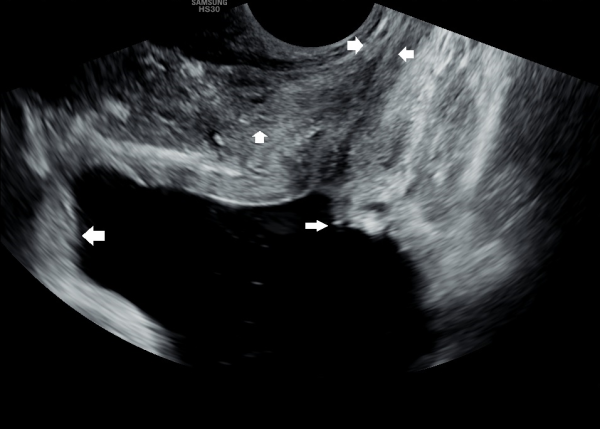

서울가정의학과의원에 첫 내원 당일 지난 5개월동안 회음부 통증과 배뇨장애로 타 비뇨기과 여러곳에서 치료를 했으나 증상의 호전이 없다고 내원 당일 검사한 경직장 전립선 초음파 검사상 사정관 입구의 석회화와 사정관의 섬유화 그리고 정낭의 낭종이 관찰되는 초음파 자료입니다.

On the first visit to Seoul Family Medicine Clinic, the patient reported having perineal pain and urination problems for the past five months, despite receiving treatment at several other urology clinics with no improvement.

A transrectal prostate ultrasound performed on the day of the visit showed calcification at the opening of the ejaculatory duct, fibrosis (scarring) of the duct itself, and cysts in the seminal vesicles.

또한 방광벽이 배뇨장애로 두꺼워져 과민성 방광이 의심되는 초음파 사진입니다.

The ultrasound image also shows that the bladder wall has become thickened, likely due to urination difficulties. This may suggest an overactive bladder, which can cause frequent or urgent urination.